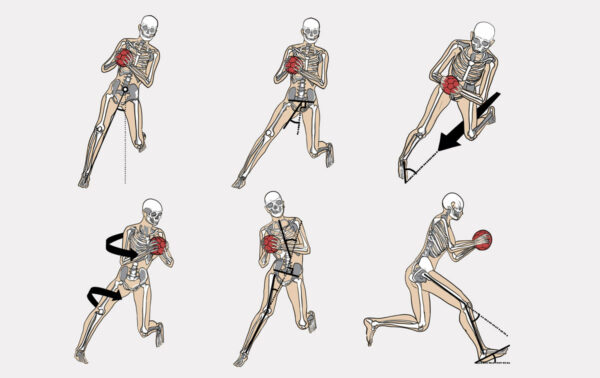

Ponadto, do urazu więzadła krzyżowego tylnego (PCL) bardzo często dochodzi podczas uprawiania sportów. Dyscypliny, w których najczęściej dochodzi do tego typu urazu to gry, w których następuje gwałtowna zmiana ruchów: od szybkiego przemieszczania się, po skręty, podskoki i wymienne przenoszenie środka ciężkości na kończyny. Do sportów, w których PCL jest narażony na uszkodzenie zaliczamy: piłkę nożną, koszykówkę, narciarstwo, sporty walki oraz sporty motorowe.

Ponadto, do urazu więzadła krzyżowego tylnego (PCL) bardzo często dochodzi podczas uprawiania sportów. Dyscypliny, w których najczęściej dochodzi do tego typu urazu to gry, w których następuje gwałtowna zmiana ruchów: od szybkiego przemieszczania się, po skręty, podskoki i wymienne przenoszenie środka ciężkości na kończyny. Do sportów, w których PCL jest narażony na uszkodzenie zaliczamy: piłkę nożną, koszykówkę, narciarstwo, sporty walki oraz sporty motorowe.